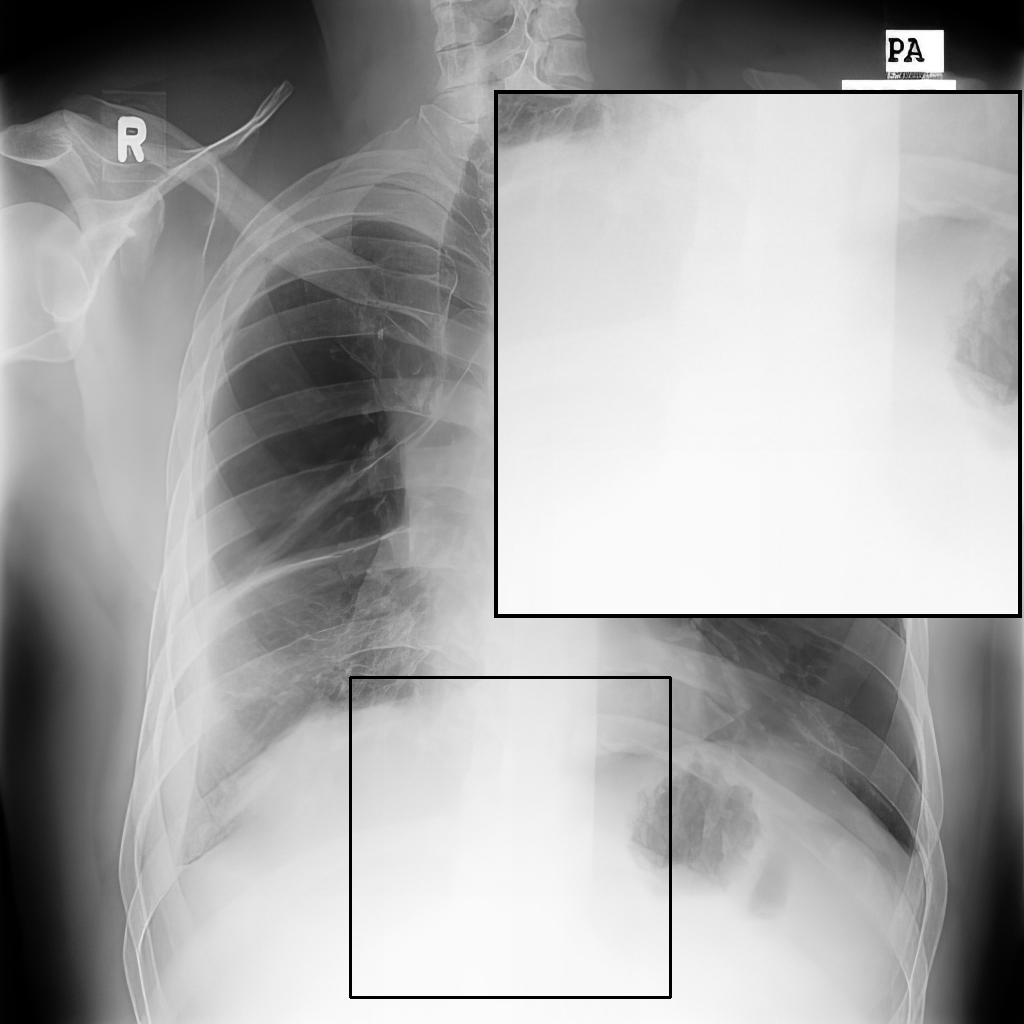

Figure 4: Visual examples of different image enhancement methods across datasets; first and second columns present results from the JSRT and Montgomery County Chest X-ray datasets, respectively, while third and fourth columns show results from the NIH Chest X-ray and CheXpert datasets

4.5 A Visual Assessment

Fig. 4 presents representative visual examples demonstrating the superiority of our method in enhancing vertebral contrast compared to several traditional and learning-based image enhancement techniques. The first and second columns show results from the JSRT and Montgomery County Chest X-ray datasets, while the third and fourth columns display results from the NIH ChestX-ray14 and CheXpert datasets. Across all datasets, the highlighted regions of interest (ROIs) emphasize the spinal areas, where fine structures and subtle details are critical for diagnostic assessment. Our method, XVertNet, consistently reveals clearer and more distinct spinal structures without introducing notable artifacts, preserving both global and local anatomical information. In contrast, traditional methods such as CLAHE [7] and Farbman et al. [19] often fail to enhance these subtle features effectively, either producing over-smoothed results or excessively sharpening noise. Similarly, learning-based methods such as ZSSR [43] and Madmad et al. [68] exhibit difficulties in generalizing across different datasets, leading to either insufficient enhancement or visible artifacts. Zero-DCE [33], although effective for natural images, struggles to adapt to the uniform and low-contrast nature of medical X-rays and was not able to supply clear enough contrast-enhanced vertebral structures.

These visual comparisons underline the clinical relevance of our approach. XVertNet successfully enhances diagnostically important structures, particularly in challenging anatomical regions like the spine, where competing methods either distort the features or fail to sufficiently reveal them. This highlights the value of integrating targeted enhancement strategies that are specifically tailored to the unique characteristics of medical imaging data.